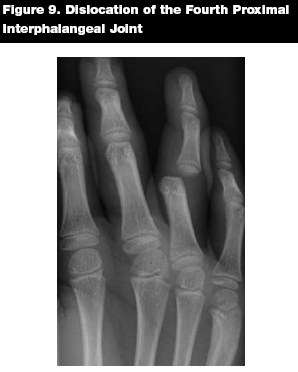

Epidemiology. The interphalangeal (IP) joints of the fingers are the most commonly dislocated joints in the body.15 Dislocations of the interphalangeal joint of the thumb, however, are uncommon.13

Patterns of Injury. Trauma and athletic injuries are common causes of IP joint injuries. Most IP joint dislocations are dorsal, meaning that the more distal bone is dorsally displaced in relation to the proximal bone. Lateral dislocations also commonly occur. Rarely, the distal bone will be displaced toward the palmar aspect of the hand, producing the uncommon volar IP joint displacement.25

Management. Dorsal dislocations are reduced with distal traction and pressure in a volar direction to the dislocated bone. (See Figures 9 and 10.) Digital nerve block allows for a painless reduction, but may not be necessary if the patient presents less than one hour after dislocating the joint.15 After relocating the joint, the affected digit should be splinted or buddy taped to the adjacent finger.

![]() |

Volar dislocations can be more difficult to reduce in the ED, and may require consultation with the hand surgeon. Reduction may be attempted with distal traction and dorsal pressure on the dislocated bone.26 Assuming a successful reduction, the subspecialist will typically splint the injured digit in extension for six weeks.15

Key Points. Dorsal IP dislocations are more common than volar IP dislocations. Pre- and post-reduction radiographs should be obtained. Splint the affected digit after reduction. Volar dislocations may require referral to a hand surgeon for definitive management.